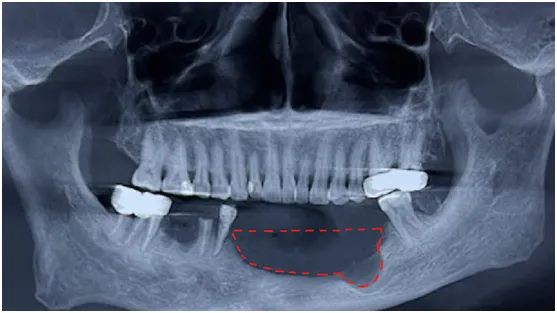

“医生,我牙还没拔,怎么骨头就少了一大块!”如果你也有过这种“骨头被吃掉”的惊悚体验,别慌,你可能遇到了“隐形刺客”——颌骨囊肿。

想象你的牙齿是个小工人,每天辛苦帮你嚼饭。但如果它被蛀虫(龋齿)咬出洞,或者牙神经(牙髓)发炎,就会变成“暴躁老哥”。炎症顺着牙根钻进骨头,像往气球里吹气一样,把骨头撑出一个囊腔——这就是根尖周囊肿(最常见的颌骨囊肿,约占60%)。

1. 定期“查户口”:每年洗牙时让医生拍张全景片,囊肿早期像玻璃上的小水珠,一拍就现形。